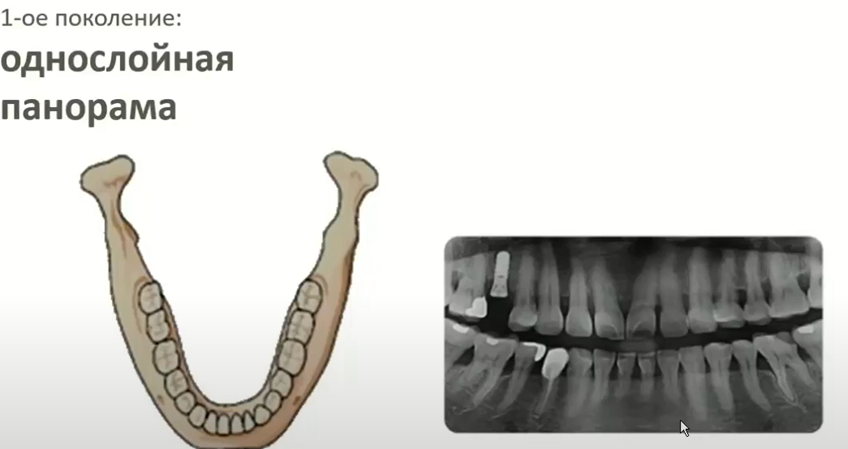

1. Первое поколение: однослойная панорама. В результате съемки на экране компьютера появляется панорамное изображение, резкость которого зависит от точности позиционирования пациента и настройки положения лазерного луча на клык. В данном случае требуется внимательно следить за положением головы как в наклоне вперед/назад, так и влево/вправо. Для настройки положения фокусного слоя и, таким образом, адаптации аппарата под прикус конкретного пациента, контролируется положение верхнего клыка. Недостаток такого метода связан с большим количеством факторов, которые влияют на качество снимка. Самым важным фактором является нестандартная форма зубной дуги, асимметрия, слишком сильный наклон верхних зубов относительно горизонтали.

Снимок из презентации Vatech